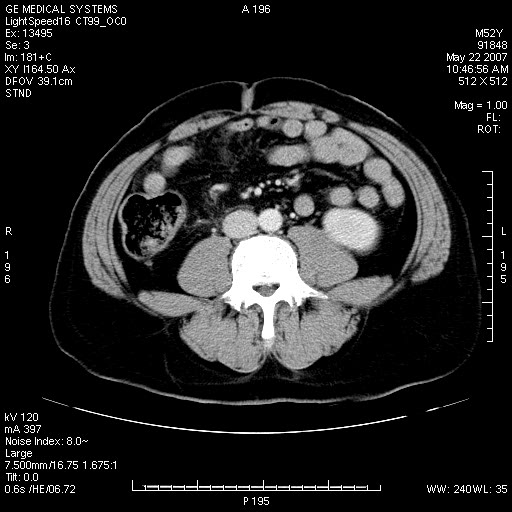

以下是引用余辉在2007-5-22 20:12:00的发言:[br]升结肠管壁明显增厚,增强有静脉期持续增强,结合患者病史,考虑结肠癌可能性大,临近脂肪影密度增高,混浊,恐有肠系膜浸润转移,建议镜检

以下是引用gaoxiao在2007-5-22 20:49:00的发言:[br]考虑升结肠癌向周围侵犯,胰头钩突受侵。

以下是引用dyqct在2007-5-22 20:43:00的发言:[br]支持结肠肝曲占位性病变(浸润型结肠癌可能性大)。胆总管下端扩张,原因待查。